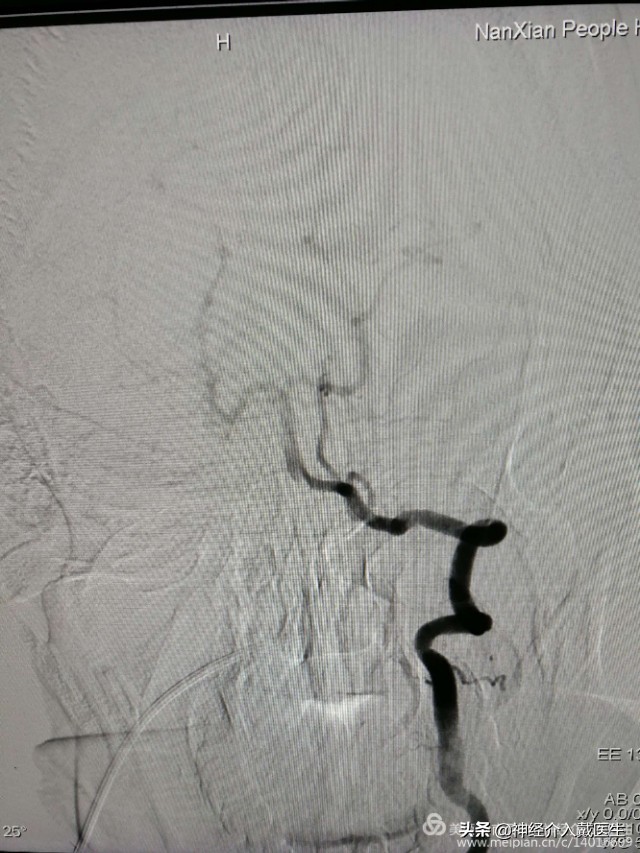

脑血管造影显示右侧椎动脉V4段动脉瘤,并且是比较少见的夹层动脉瘤。长度大约9mm,动脉瘤破口与右侧椎动脉重要分支右侧小脑后下动脉很近。